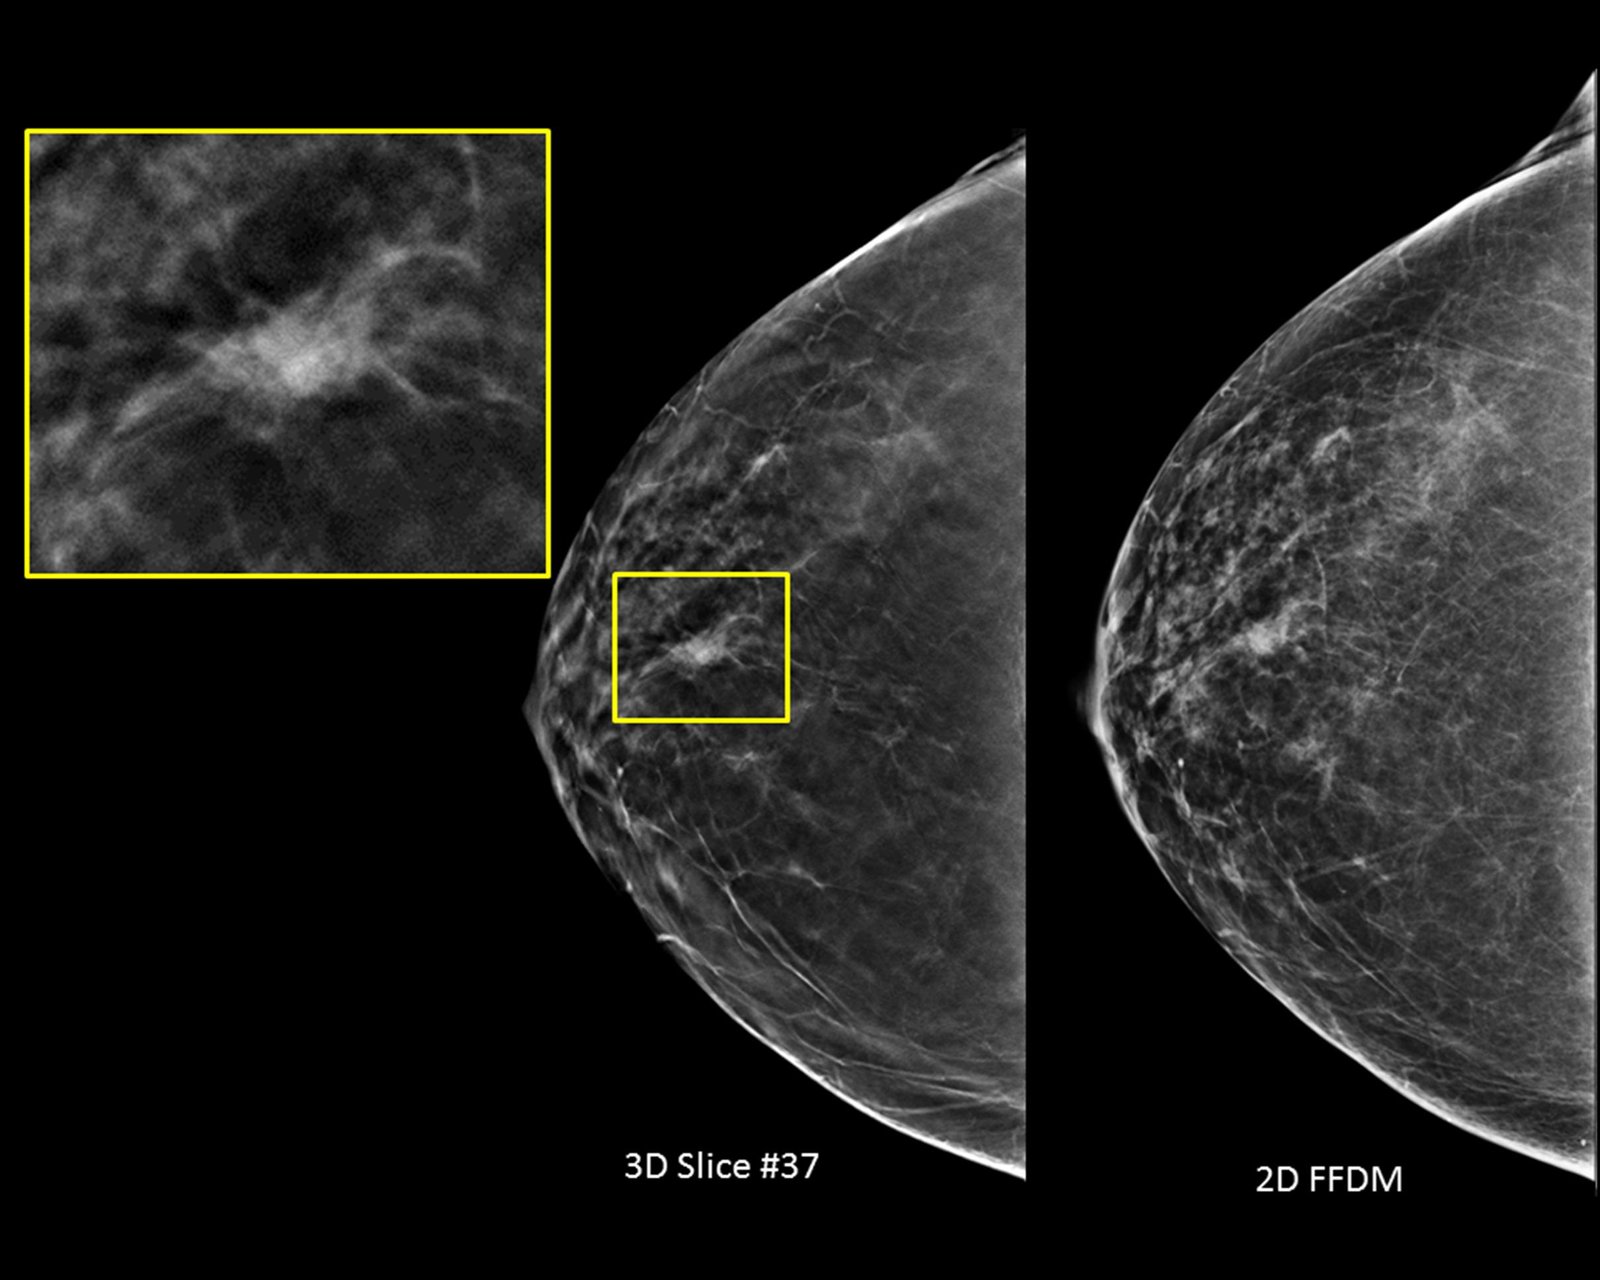

Better visibility

Designed to improve visibility of fine details for greater diagnostic confidence.*

* is compared to 2D alone